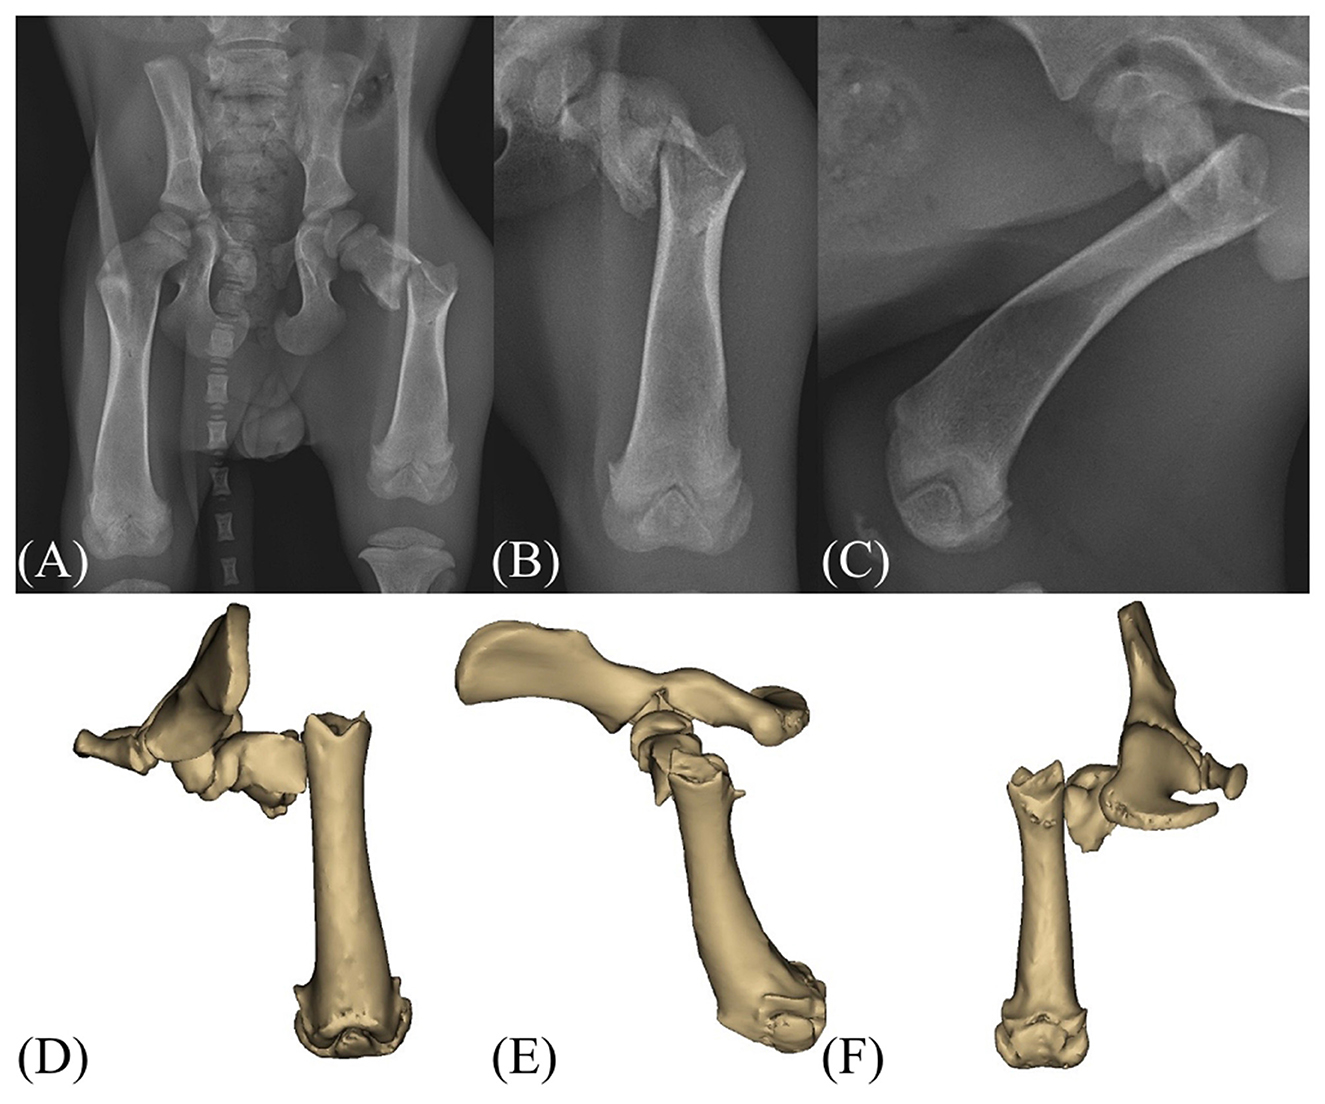

This case report describes the successful management of a subtrochanteric femoral fracture in a 2-month-old dog using temporary supratrochanteric plate fixation, performed prior to the development of the greater trochanter apophysis. A tibial plateau leveling osteotomy plate was applied to the proximolateral femur and subsequently removed following radiographic evidence of bridging callus formation. At the 21-month follow-up, the dog exhibited normal limb function, symmetrical femoral length, and appropriate development of the greater trochanter. Although a mild procurvatum deformity was noted, no clinical signs or range of motion deficits were observed. These findings support the use of temporary fixation across the trochanteric region as a feasible treatment strategy for immature subtrochanteric femoral fractures when performed prior to apophyseal development.